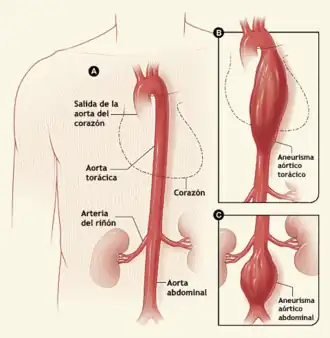

Un aneurisma es una pequeña protuberancia con forma de globo y llena de sangre que se forma en las paredes de los vasos sanguíneos.[1] Cualquier vaso puede presentarlo pero es más común en la arteria aorta, los vasos cerebrales, la arteria poplítea, la arteria mesentérica y la arteria esplénica.[2]

Un aneurisma cerebral puede ocurrir en venas o arterias de la base del cerebro (en el polígono de Willis) y un aneurisma aórtico ocurre en la arteria principal que lleva sangre desde el ventrículo izquierdo del corazón al cerebro. Cuando el tamaño de un aneurisma aumenta, hay un riesgo significativo de rotura, lo que puede resultar en hemorragias graves, otras complicaciones o muerte. Los aneurismas pueden ser hereditarios o causados por enfermedades que debilitan las paredes de los vasos sanguíneos.

Muchos aneurismas intracraneales no surgen distal al origen de las arterias renales a la aorta abdominal infrarrenal. Sin embargo, la evidencia creciente sugiere que aneurismas aórticos abdominales son una patología totalmente separada.

La aorta torácica también puede estar involucrada. Una forma común de aneurisma aórtico torácico implica el ensanchamiento de la aorta proximal y de la raíz de la aorta, lo que conduce a una insuficiencia aórtica. Los aneurismas pueden también ocurrir en las piernas, especialmente en los vasos profundos (por ejemplo, los vasos poplíteos en la rodilla).

Aneurismas aórticos y periféricos

Para los aneurismas de la aorta, brazos, piernas, o cabeza, la sección debilitada del vaso puede ser sustituido por un injerto de derivación que se sutura a los muñones vasculares. En lugar de costura, los extremos del tubo de injerto, hechas rígidas y expandible de nitinol alambre, se pueden insertar fácilmente en su diámetro reducido en los muñones vasculares y luego expandido hasta el diámetro más apropiado y permanentemente fijados allí por ligadura externa.[18][19]